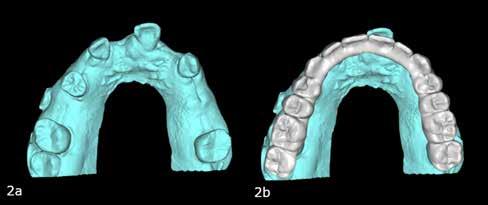

Cikkünkben összesen négy, kétrészes kerámiaimplantátum klinikai és radiológiai eredményeit mutatjuk be, amelyeket a felső, moláris régióba helyeztünk be.

A műtéti tervezéshez mindkét esetben CBCT-felvételt használtunk, majd az utánkövetési időszakban periapikális röntgenfelvételekkel ellenőriztük az implantátumokat. A fogeltávolítást követően azonnali implantáció történt, az alveolus fala és az implantátum felszíne közt fennmaradó réseket csontpótlóval töltöttük ki. A három hónapos gyógyulás leteltével az ideiglenes koronákat eltávolítottuk, A-szilikonnal lenyomatot vettünk, majd három lítium-diszilikát és egy monolitikus cirkónium-dioxid korona készült. A páciensek utánkövetése mindkét esetben minimum tizenkét hónap volt, amelynek során valamennyi implantátumot klinikailag és radiológiailag is sikeresnek ítéltünk az osszeointegráció, a marginális csont stabilitása és a periimplantáris szövetek egészsége tekintetében.

Mindkét páciens 2023 márciusában jelentkezett a brazíliai Rio de Janeiróban található Sobre-Implantes magánklinikán. Fogászati implantátumokkal történő rehabilitációt szerettek volna (azonnali vagy késleltetett implantációval, azonnali ter-

heléssel vagy anélkül). Az első páciensnél gyökérreszorpció miatt szükségessé vált a jobb felső premolárisok és az első moláris eltávolítása (1. a–b ábrák). A második páciensnél a bal felső második premoláris frakturát szenvedett (1. c–d ábrák) Az átfogó tervezést és diagnosztikát CBCT-felvétel segítségével végeztük (2. a–c ábrák), a posztoperatív kontroll és az utánkövetés időszakában pedig periapikális röntgenfelvételeket készítettünk. A jelen tanulmányban résztvevő valamennyi páciens nemdohányzó volt, jó, vagy gyógyszeresen jól karbantartott általános egészségi állapotnak örvendett. A hatékony plakk-kontroll ellenére műtét előtt mindkét páciensnél végeztünk supragingivális depurálást és gyökérsimítást.

3. a–b ábrák: Fogeltávolítást követő alveolus prezerváció. – 4. a–b ábrák: Az implantátumok beültetése.

5. a–b ábrák: A behelyezett implantátumok okkluzális nézetből. – 6. ábra: Az implantátum és a csontpótló anyag.

2. a–c ábrák: Kiindulási CBCT-felvételek.

7. a–b ábrák: Az implantátumok ideiglenes fejei és az azonnali ideiglenes koronák okkluzális nézetből. – 7. c ábra: A bal felső második premoláris ideiglenes koronája. – 8. a–c ábrák: Hagyományos, zárt kanalas lenyomatvétel A-szilikonnal a jobb felső 4–6 implantátumok lemintázására. – 9. a–c ábrák: Hagyományos, zárt kanalas lenyomatvétel A-szilikonnal és folyékony kompozittal.